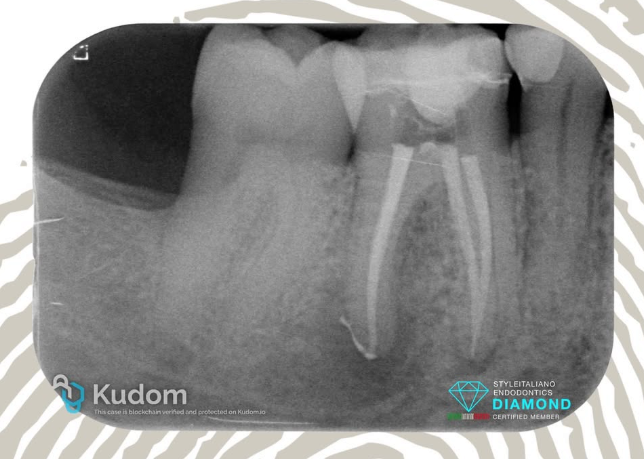

3.5: Necrosis - Lesion - Lip Paresthesia - Ledge - 4 years recall

Patient referred for treatment of a necrotic tooth 3.5 with associated periapical lesion. The patient initially presented with an acute abscess, pain, and lip paresthesia due to compression of the mental nerve. Despite an initial dressing performed by the referring dentist and antibiotic therapy, symptoms persisted.

Endodontic treatment was initiated by the referring colleague, but he was unable to determine the working length due to the formation of a ledge in the apical third of the canal.

After successful management of the ledge, the canal was medicated with calcium hydroxide. Two weeks later, all symptoms had resolved completely, and the tooth was obturated using CeraSeal bioceramic sealer with the Cold Hydraulic Condensation technique.

The post-operative radiograph shows the presence of the previously created ledge completely filled by the bioceramic sealer.

Recall at 4 years shows the complete healing of the lesion.